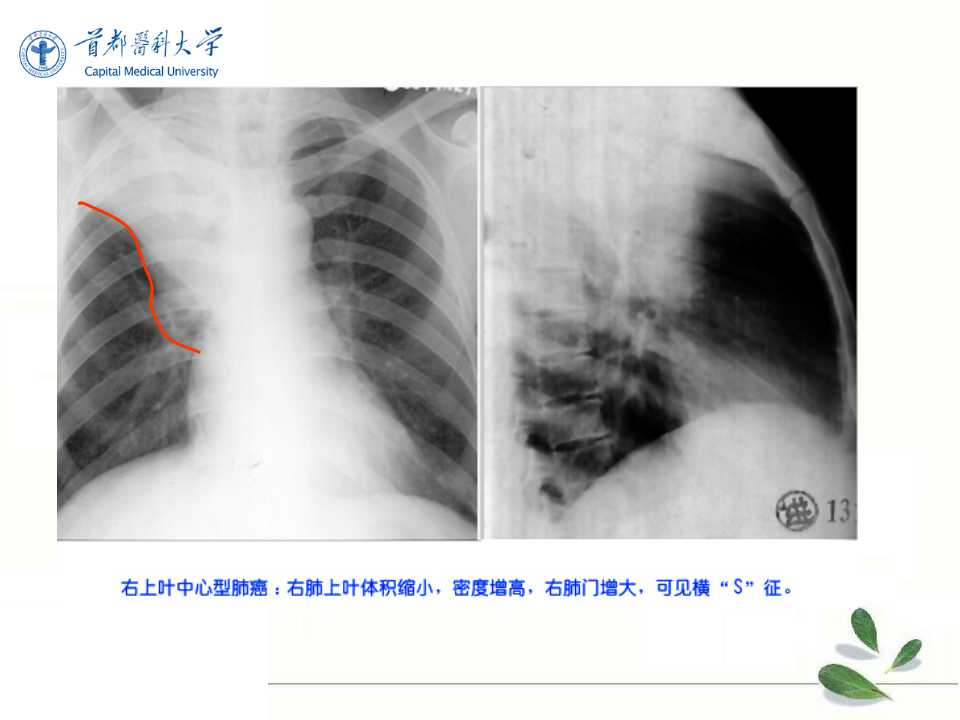

肺癌的影像学检查